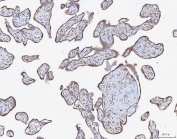

IHC staining of FFPE human placenta tissue with ATX2 antibody. HIER: boil tissue sections in pH8 EDTA for 20 min and allow to cool before testing.